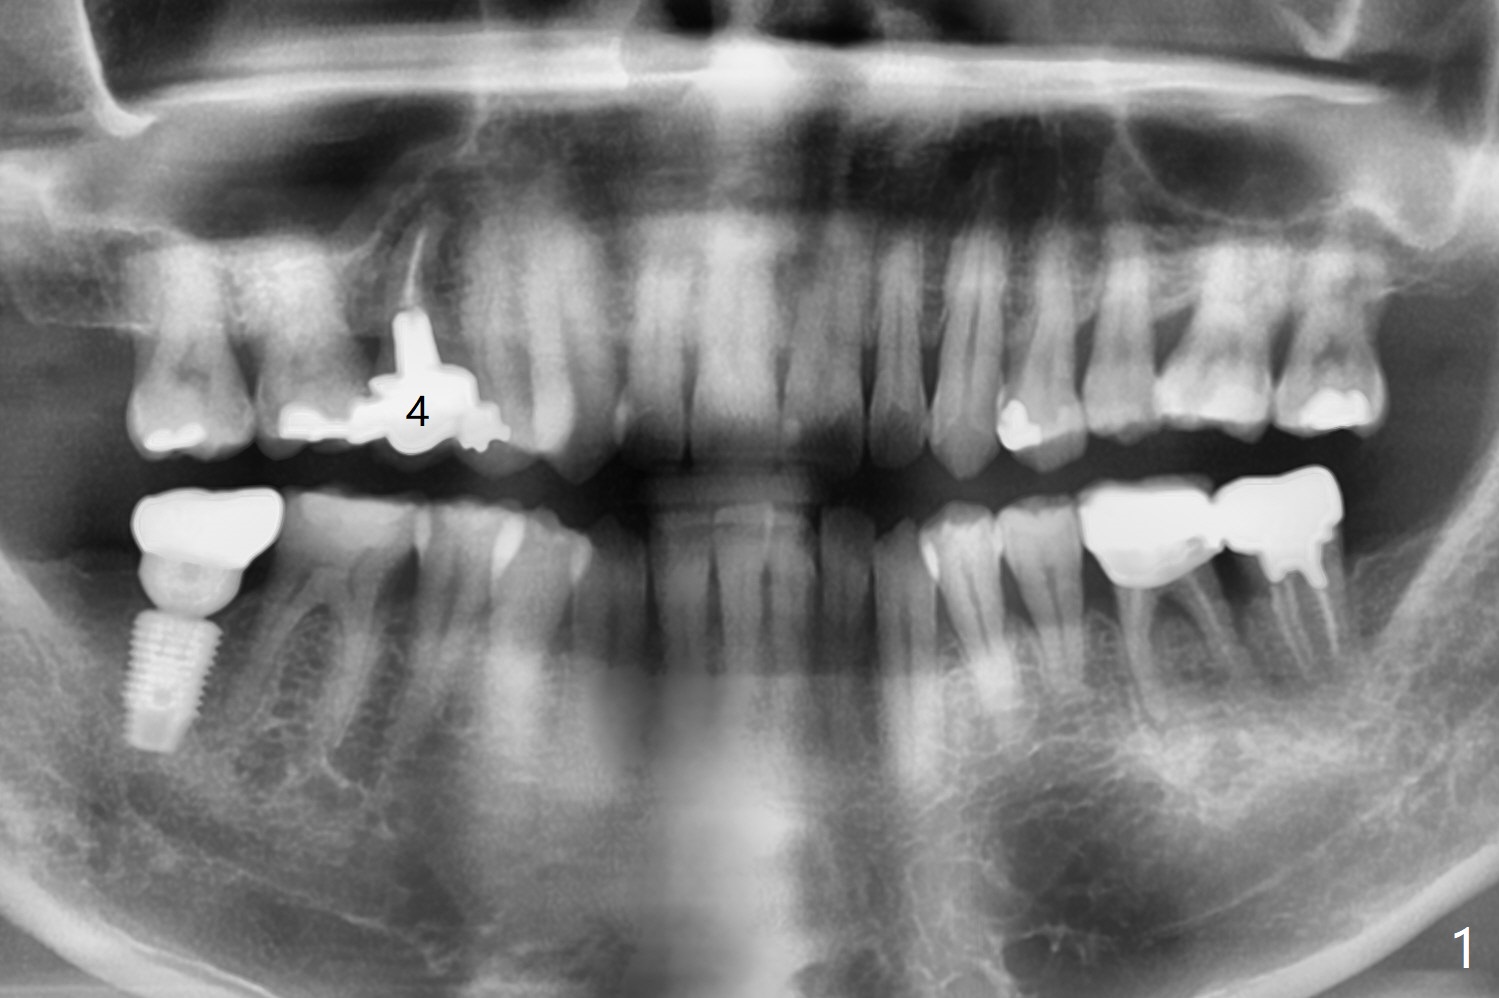

A 48-year-old man has had palatal and buccal abscesses at #4 for 6 and 1 months, respectively (Fig.1). The patient loves bubble gums. There is a post at #4 (Fig.2). CBCT shows apical buccal and palatal defects (Fig.3,4). There are no deep periodontal pockets. The tooth has mobility II. No guide is fabricated so that we have options to do bone graft or immediate implant after extraction, depending on extent of bone defects. Later impression is taken for guide. Use UF implant 4.5x10 mm with sinus lift (PRF membranesx2).